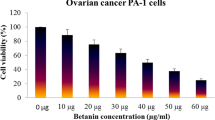

Sulforhodamine B test

The A. vasica extract was further treated with PA 1 cell line to check its anticancer effect. The anticancer ability was initially evaluated using SRB staining assay for the cells treated with different concentrations of the A. vasica extract, which were initially visualized under a phase contrast microscope for detecting the morphological changes seen in the cells treated with higher concentrations of the extract.

The SRB assay was done to measure drug-induced cytotoxicity and cell proliferation for drug screening applications. From the results, it is observed that as the concentration of the A. vasica extract increased for treatment, the percentage viability of PA1 cancer cells decreased linearly. This observation might highlight the potential anticancer effect of the extract with a LC 50 value of 107.339 μg/ml (calculated using ED50 PLUS V1.0 Software as illustrated in Figs. 2 and 3). As seen in Fig. 2, a gradual decrease in the number of cells (B, C, D, E, and F) and also the morphological changes induced by the extract on PA1 cells such as membrane blebbing, cell shrinkage, etc. when compared to the untreated control (A) indicate the cytotoxic effect of the extract.

The ovarian teratocarcinoma cell line PA-1 demonstrated a single chromosomal aberration and is reported to be a useful model cell line used to demonstrate the anticancer efficacy of the investigated agent in in vitro studies [27,28,29]. Our results clearly showed a decrease in cell viability as per the method of SRB with an LC 50 value of 107.33 μg/ml. The SRB assay has been used since its development in 1990 [30] to inexpensively conduct various screening assays to investigate cytotoxicity in cell-based studies [31]. This method relies on the property of SRB, which binds stoichiometrically to proteins under mild acidic conditions which could be extracted using basic conditions; thus, the amount of bound dye can be used as a proxy for cell mass, which can be extrapolated to measure cell proliferation; hence, EAV is an efficient maneuver to measure the proliferation path of PA1 cell line along with considerable morphological changes similar to that of apoptosis [32].